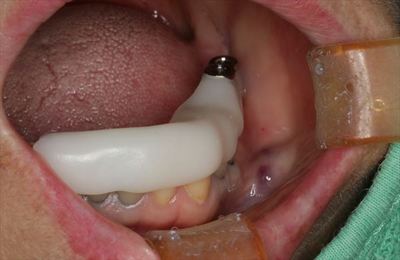

サージカルステントの適合は良好です。

サージカルステントを用いてパイロットドリルでドリリングし深度ゲージを挿入して

レントゲンを撮影します。